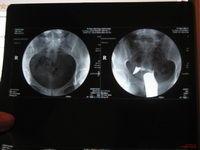

[1]输卵管积水是由于输卵管伞端的梗阻形成的,而输卵管伞端的梗阻是由于病原体感染引起输卵管炎症造成的,由于细菌的感染,白细胞的浸润形成内膜肿胀、间质水肿、渗出,输卵管粘膜上皮脱落。又由于周围纤维组织的增生包裹和肉芽组织的机化使粘膜粘连或伞端粘连,导致输卵管不通,当输卵管伞端粘连时,就形成了伞端的梗阻。也有的液体被吸收剩下一个空壳,当做造影时显示出积水影。